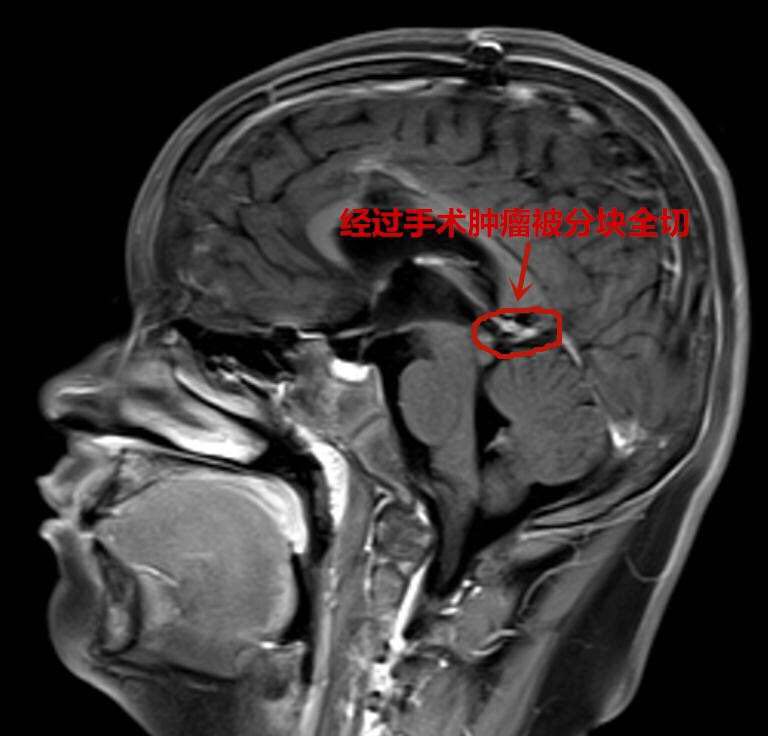

为求进一步治疗,当天夜里他们便辗转到武汉脑科医院·长江航运总医院小儿神经外科。此时,军军随时都有生命危险,该科专家邵强主任连夜组织急诊手术。好在通过抢救及时保住了孩子的生命,一周后随着颅内压降低,邵强团队为军军进行了开颅手术,进行了分块全切脑瘤。邵强称,虽然患儿的肿瘤体积不大,但稍有不慎就会损伤正常脑组织和血管,引发昏迷,甚至大出血,可谓危险重重。

目前,通过病理报告证实,军军的脑瘤为先天性皮样囊肿属良性肿瘤,全切后一般不会复发。经术后恢复,他已完全恢复正常,不长即可回归校园。